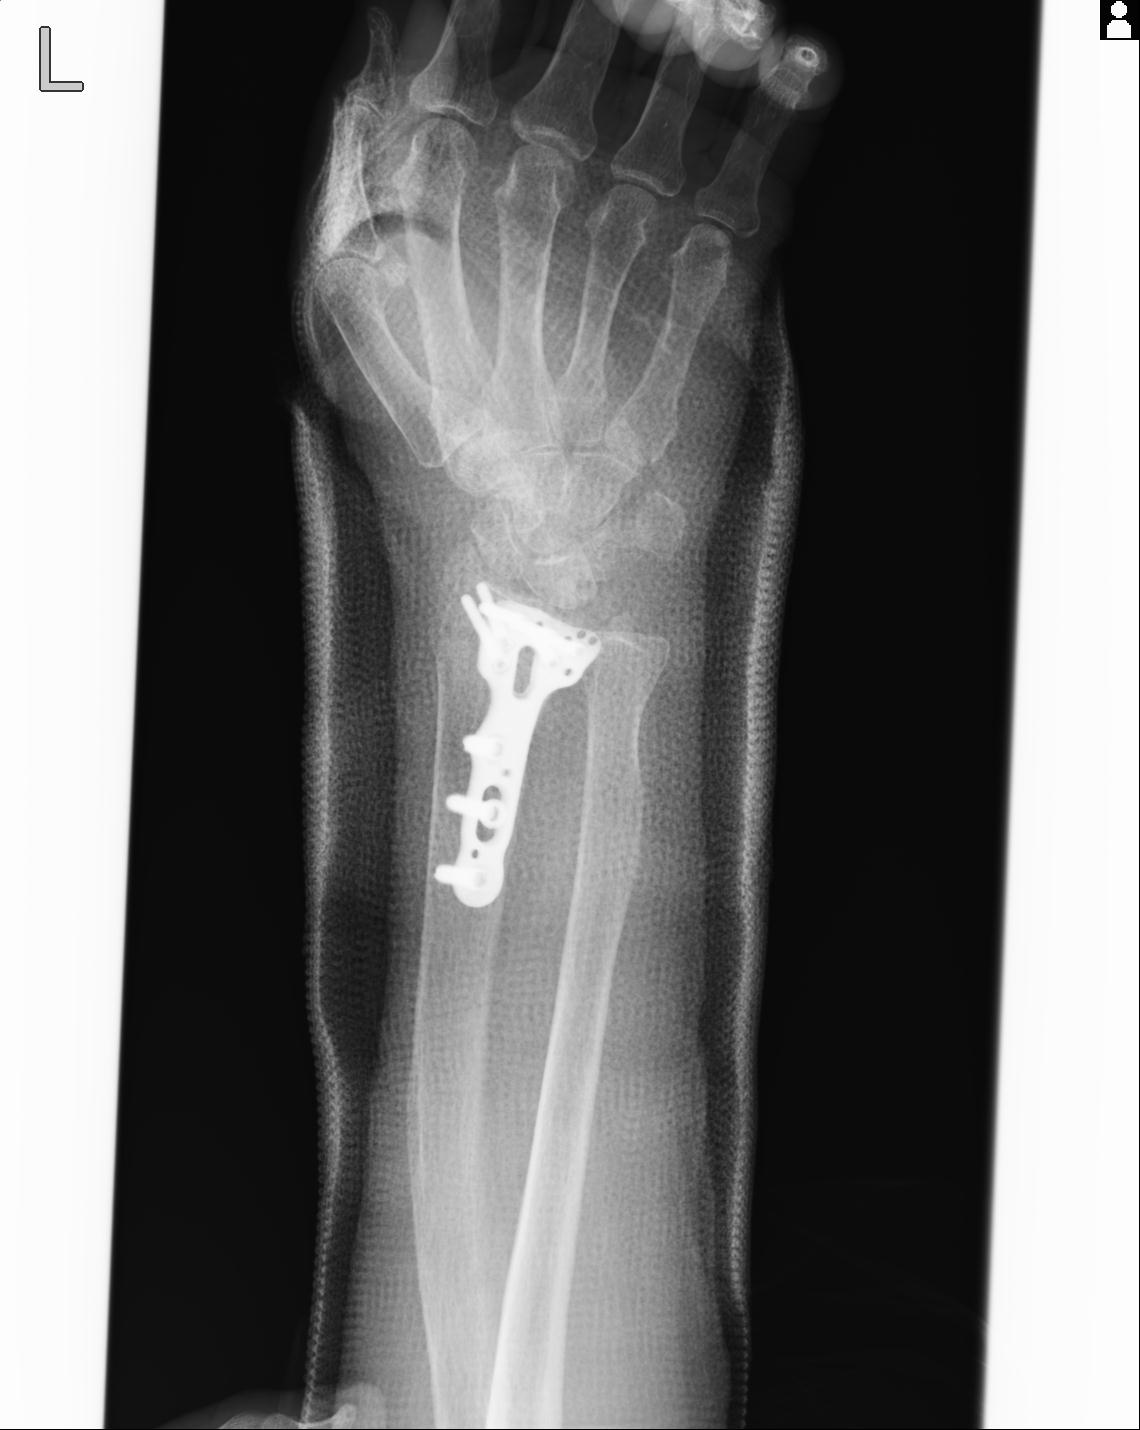

102766 1/5 1/12 左手関節 4R 28歳男性 左橈骨遠位端

102739 12/30 1/5 左手関節 4R 92歳女性 橈骨遠位端

101290 1/4 5/21 5/20 手関節 2R 17歳男性 橈骨遠位端